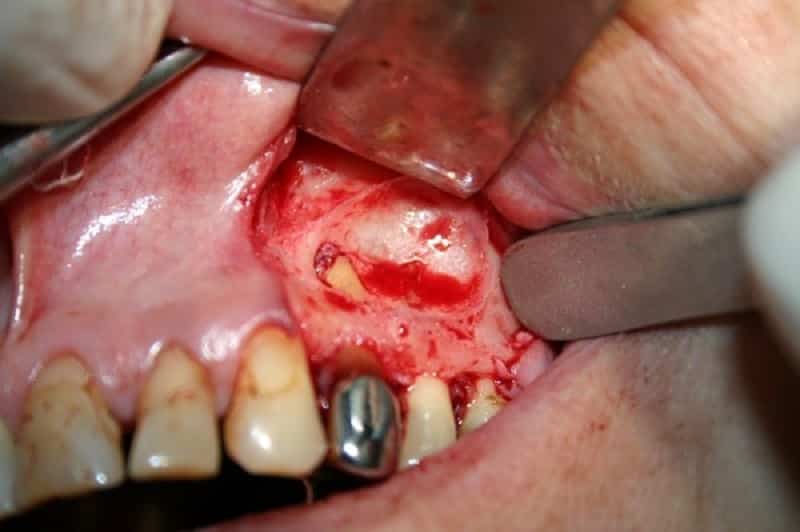

Лечение периодонтита с помощью хирургического вмешательства применяется довольно редко и, как правило, только в самых тяжелых и запущенных случаях. Этот подход включает полное или частичное удаление пораженных костных тканей, а также вскрытие области, где накапливались гнойные массы в течение болезни.

В настоящее время врачи чаще всего стремятся сохранить зуб.

При этом удалению подлежат только те его части, которые непосредственно подверглись разрушению. Оперативные методы также используются для лечения периодонтита, вызванного длительным или кратковременным воздействием определенных химических веществ. Для устранения последствий данной патологии необходимо не только удалить частицы химических соединений, но и провести обработку тканей, чтобы ликвидировать результаты негативного воздействия.